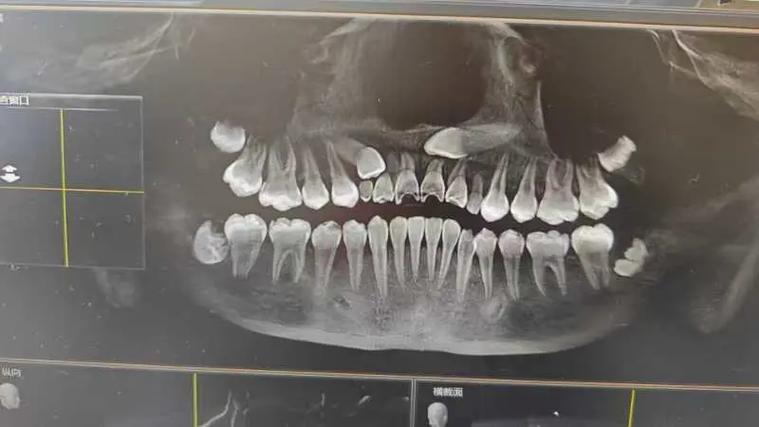

低位水平阻生齿的正畸治疗核心在于“解除阻生、引导萌出、保存功能”,通过科学设计牵引路径,将埋藏的牙齿移动至正常咬合位置,避免邻牙损害及颌骨破坏,治疗前需全面评估:临床检查需观察口腔黏膜状况、邻牙松动度及咬合关系;影像学检查是关键,通过CBCT可清晰显示阻生牙的萌出方向、牙根形态、与邻牙牙根及下颌神经管的距离,判断是否具备牵引条件;同时需研究模型分析咬合曲线,制定个性化方案。

此阶段需综合临床与影像学资料,明确阻生牙位置、萌出阻力来源(如骨阻力、邻牙阻力)及患者年龄(青少年颌骨生长潜力大,预后更佳),若邻牙已严重损坏或存在囊肿,可能需先拔除患牙,再对阻生齿进行牵引;若邻牙健康,则需设计支抗,为后续牵引提供稳定基础。

在局麻下于阻生牙牙冠顶部切开黏膜,去除部分骨质,暴露牙冠并粘接牵引钩,随后用镍钛丝或橡皮圈将牵引钩与矫治器连接,施加轻柔持续的力量(50-70g),每周复诊调整牵引方向,牵引过程中需密切观察牙根吸收情况,若出现明显吸收,需暂停牵引或调整力值。

预后方面,多数低位水平阻生齿通过规范正畸牵引可成功萌出并行使功能,但若阻生牙位置过深、牙根弯曲或与神经管距离<1mm,可能需结合外科手术辅助,甚至无法保留而拔除,青少年患者因颌骨生长活跃,治疗周期更短,效果更佳;成年人则需更长时间保持,以防止复发。